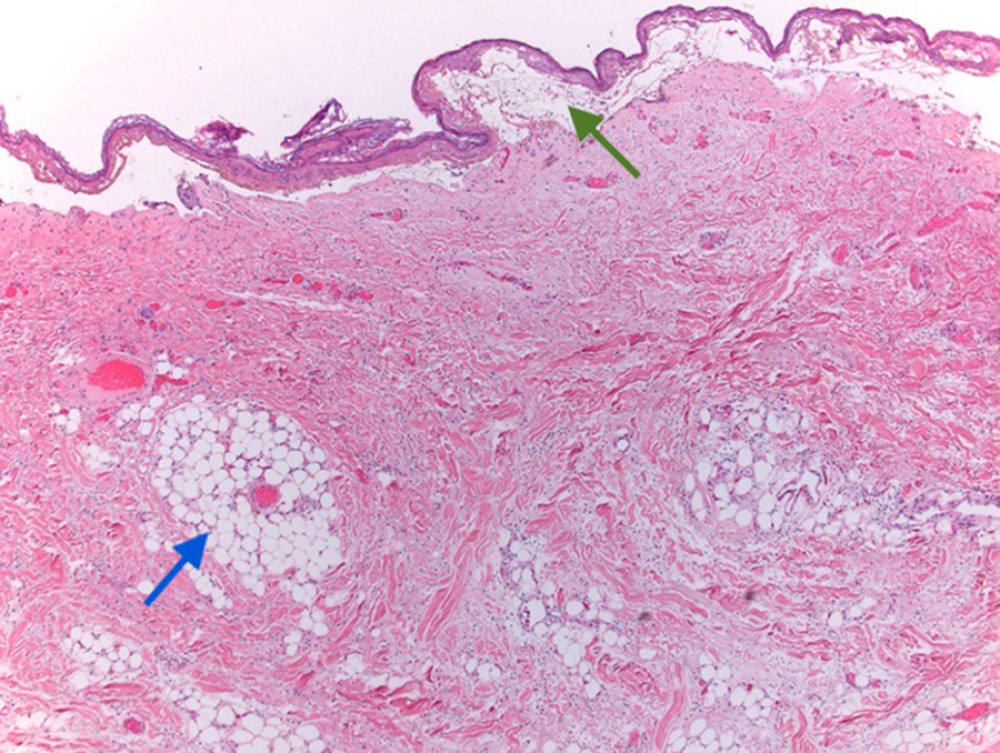

From amjcaserep.com

American Journal of Case Reports Nevus Lipomatosus Superficialis in a Foam Cells Nevus — balloon cell nevus (bcn) is a histopathological variant of cutaneous acquired melanocytic nevi characterized. — nevi are benign melanocytic tumors that can be broadly divided into those that arise in utero (congenital) and those that are acquired after birth. the presence of foam cells in the connective tissue papillae between the epithelial rete ridges forms the. Foam Cells Nevus.

Foam cells are present in the papillary dermis (H and E X 400 Foam Cells Nevus — balloon cell nevus (bcn) is a histopathological variant of cutaneous acquired melanocytic nevi characterized. the presence of foam cells in the connective tissue papillae between the epithelial rete ridges forms the hallmark in its diagnosis. while the mechanisms leading to foam cell death have not been detailed in tuberculosis, it is clear that foam cells can. Foam Cells Nevus.